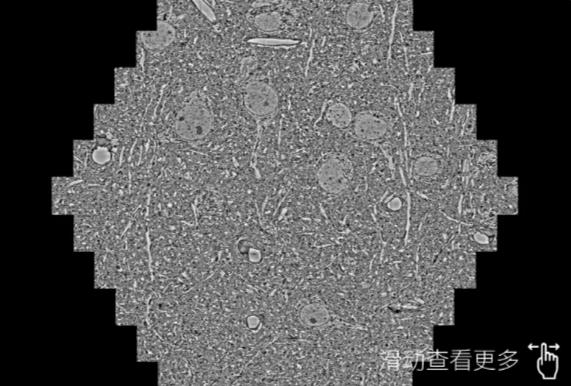

鼠脑切片。左图使用广东蔡司广东扫描电镜MultiSEM706对165μmx143pm面积区域成像,耗时仅需1.5秒。右图为鼠脑切片中30μm区域放大效果。样品由芝加哥大学B.Kasthuri提供。

使用蔡司高速广东扫描电镜MultiSEM对1mm²人脑皮层组织进行高分辨成像,并对其中的各种细胞结构进行三维重构分析。左图展示了2x3mm²组织平面中锥体神经元的三维重构效果。右图显示了局部体积神经元三维重构。图像由哈佛大学chtman实验室提供,渲染图由D. Berger 制作。